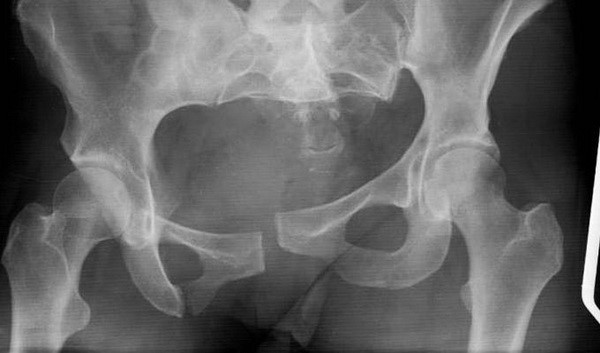

Основным методом диагностики является рентген в двух или трех проекциях. С помощью этого исследования можно узнать о количестве переломов, их локализации, целостности тазового кольца, наличии отломков.

Если необходима дополнительная информация о состоянии связок, суставов, наличии мелких трещин, используются современные методы: компьютерная или магнитно-резонансная томография.

В обязательном порядке проводится ультразвуковое исследования органов брюшной полости, малого таза. Настораживают свободная жидкость в брюшной полости, размытые, искаженные контуры органов.